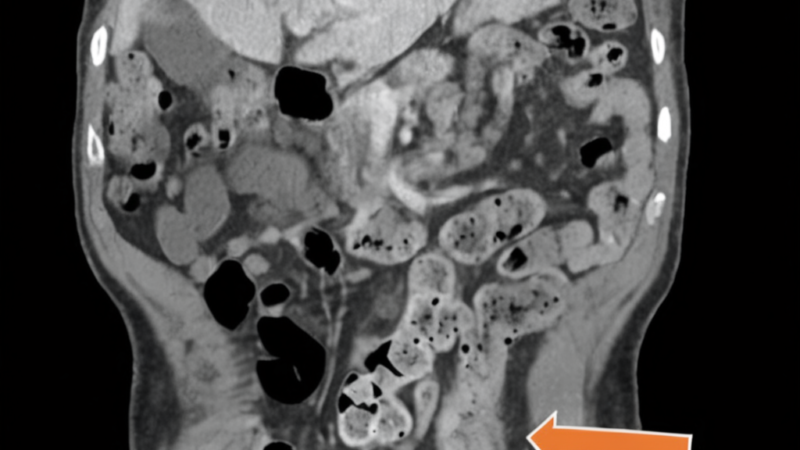

Initially treated for presumed Behçet’s disease with corticosteroids and immunomodulatory therapy, the patient experienced only partial improvement. Over several months, his condition deteriorated dramatically, culminating in severe abdominal pain and a life-threatening bowel perforation. Emergency surgery revealed the true diagnosis: Crohn’s colitis, not Behçet’s disease.

The diagnostic breakthrough came through histopathologic examination during surgery, which showed the characteristic transmural inflammation of Crohn’s disease without the vasculitis typically seen in Behçet’s disease. Following the correct diagnosis, the patient was started on infliximab therapy and achieved clinical stabilization.

The progression to bowel perforation in this case is particularly sobering. Perforation represents one of the most serious complications of Crohn’s disease, occurring when inflammation weakens the intestinal wall to the point of rupture. This complication carries significant risks, including peritonitis, sepsis, and even death if not treated promptly. The fact that this patient’s perforation might have been prevented with earlier, appropriate IBD treatment underscores the stakes involved in accurate diagnosis.

This case also highlights the critical role of tissue biopsy and histopathologic examination in differentiating between similar conditions. While blood tests, imaging, and clinical presentation provide important clues, sometimes definitive diagnosis requires examining actual tissue samples under a microscope. For people with IBD, this reinforces why procedures like colonoscopy with biopsy remain the gold standard for diagnosis and monitoring.